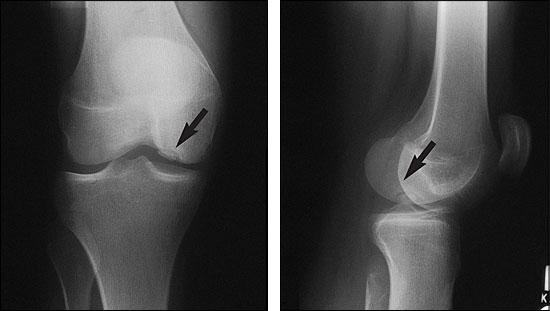

Evaluarea inițială se bazează pe anamneză detaliată și examen clinic, care pot evidenția durere localizată, sensibilitate la palpare, limitarea mișcării sau simptome mecanice precum blocajul articular. Aceste elemente, interpretate în contextul istoricului de activitate fizică sau traumatisme, pot sugera suspiciunea de osteocondrita; este important ca evaluarea să fie realizată de un specialist care poate pune în discuție și diagnostice diferențiale relevante.

Investigațiile imagistice completează examenul clinic: radiografia simplă poate indica modificări osoase, iar imagistica prin rezonanță magnetică poate oferi informații despre cartilaj și edemul osos; în cazuri selectate, CT sau scintigrafia osoasă pot contribui la clarificare, iar artroscopia poate fi atât diagnostică, cât și terapeutică. Interpretarea rezultatelor și decizia privind următorii pași trebuie făcută individualizat de către medic; pentru resurse suplimentare, consultați informații despre osteocondrita.